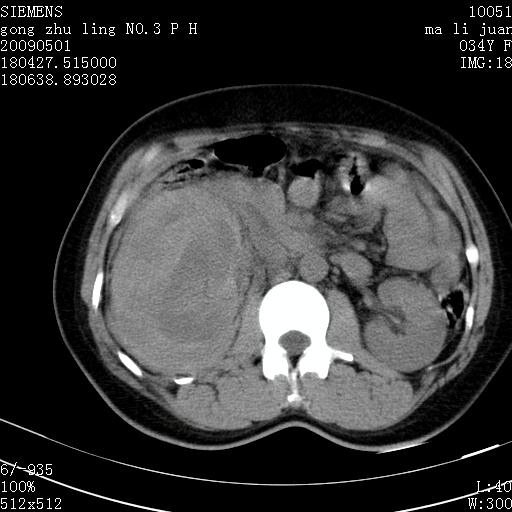

标题: CT19733:右肾碎裂

青年女性,骑摩托车摔伤。

右肾碎裂伤,包膜下血肿。

术中仅见右肾碎裂,肾蒂血管未见断裂。

支持 右肾破裂伴肾包膜下及肾周血肿。

右肾破裂并右侧腹膜后间隙出血。